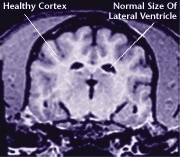

The ageing process attacks all body systems and organs in a dog, including the brain. The result is a loss of brain function, and often, the appearance of behavioural changes that were not present in a dog’s younger years.

![]() Healthy Older Brain | ![]() Older Brain with Damage |

| MRI scans show loss of brain tissue in affected dogs. Note: MRI scans are not harmful to dogs. | |